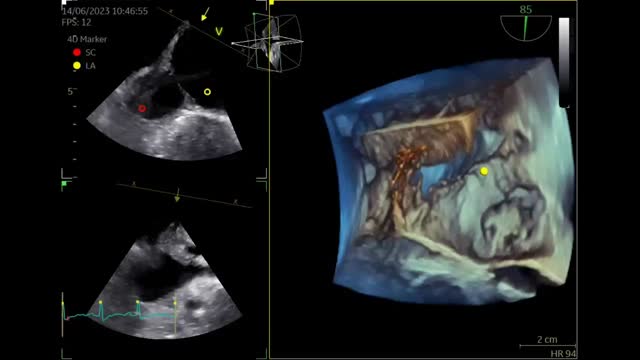

Besides her known conditions, the TTE showed a dilated coronary sinus (CS) and right ventricle that was not proportional to the MR. Transesophageal echocardiography (TEE) revealed prolapse of the mitral valve anterior leaflet (Figure 1A). The CS was markedly dilated, with no opacification after saline injection (Figure 1B). There was echo dropout in the left atrial wall and communication with the CS, raising the suspicion of unroofed CS (URCS) atrial septal defect (ASD). Three-dimensional echocardiography showed absence of the CS wall (Figure 1C) and the already known PFO (Figure 1D). Coronary computed tomography angiography (CCTA) confirmed the diagnosis of URCS (Figure 1E and F). Right catheterization showed a cardiac index of 11.47 l/min/m2, pulmonary artery pressure of 47 mmHg, and significant left-to-right shunt (Qp/Qs 2.2). The patient underwent mitral valve replacement and ASD closure. The PFO was left open. Postoperative course was uneventful and the patient was still asymptomatic at one year.

(A) Transthoracic echocardiography (TTE), parasternal long-axis view, showing the mitral valve (red arrow) and the enlarged coronary sinus (white arrow); (B) TTE, 4-chamber view, after injection of saline, without significant opacification; (C) three-dimensional echocardiography showing the coronary sinus (red dot) and left atrium (yellow dot) and revealing the absence of the coronary sinus wall; (D) transesophageal echocardiography showing the patent foramen ovale (green arrow); (E) coronary computed tomography angiography (CCTA) showing the right atrium (blue dot), left atrium (orange dot), the enlarged CS (green dot) with missing roof, communicating directly with the left atrium, and a communication between the right and left atria (purple arrow); (F) CCTA showing the right atrium (blue dot), right ventricle (white dot), left atrium (orange dot) and enlarged coronary sinus (green dot). The aorta (yellow arrow) and pulmonary artery (white arrow) can also be seen.